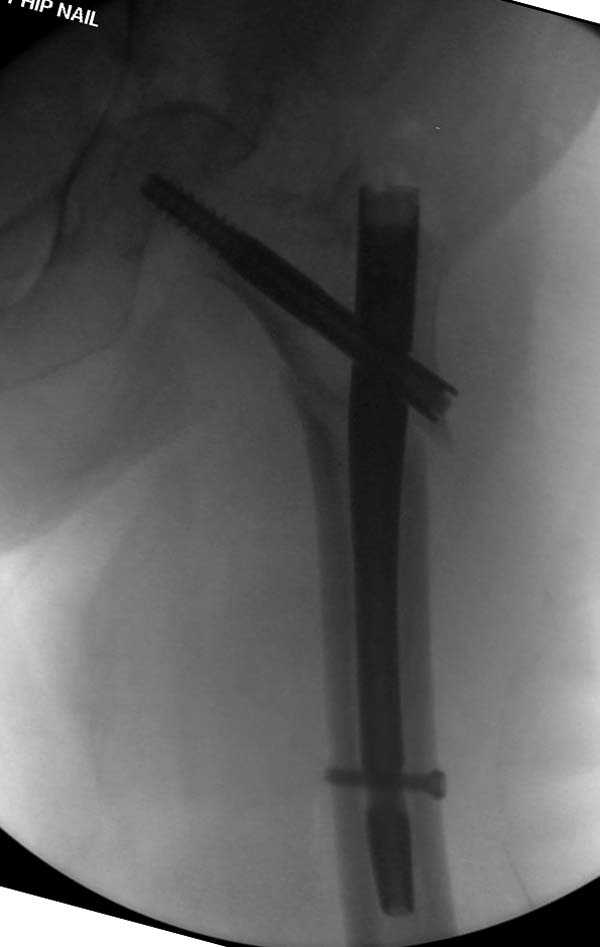

Здесь представлен случай, где в послеоперационном периоде обнаружена техническая ошибка, Gamma 3 установлен с нарушением методики. Больная в 91 лет, прооперирована через день после поступления и выписана через 48 часов.

При первом послеоперационном поликлиническом осмотре больная предъявила жалобы на боли в бедре. В серийных снимках обнаружен продольный перелом верхнего отдела бедра.

Считаем, что техническая ошибка произошла во время установки гвоздя, когда рассверливанию канала не уделили должного внимания. Канал остался узковат, и гвоздь был забит с силой. Полная нагрузка конечности приостановлена на две недели, и боли в конечности изчезли. Больная начала нагрузку и перелом срастается. -- Djoldas Kuldjanov, M.D. Associate Professor Department of Orthopedic Surgery St. Louis University